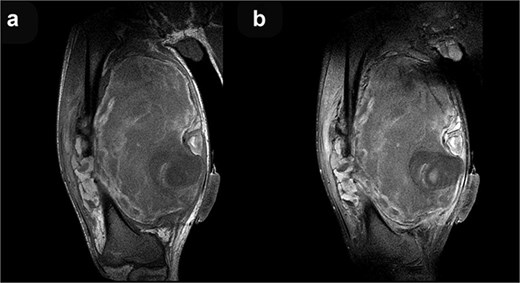

Coronal T1-weighted (a) and post-contrast T1-weighted (b) MRI sequences demonstrate no discernible contrast enhancement within the mass.